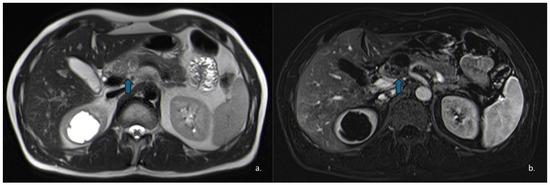

Pancreatic Cystic Lesions: From Basic Knowledge to Recent Guidelines

by Ginevra Danti, Ludovica Scalzone, Lavinia Mattolini, Matilde Anichini, Francesca Treballi, Linda Calistri, Diletta Cozzi and Vittorio Miele

Pancreatic cystic lesions (PCLs) are increasingly detected due to widespread use of cross-sectional imaging. They encompass a heterogeneous group of lesions, ranging from benign pseudocysts and serous cystic neoplasms (SCNs) to premalignant mucinous cystic neoplasms (MCNs) and intraductal papillary mucinous neoplasms (IPMNs), as [...] Read more.

Pancreatic cystic lesions (PCLs) are increasingly detected due to widespread use of cross-sectional imaging. They encompass a heterogeneous group of lesions, ranging from benign pseudocysts and serous cystic neoplasms (SCNs) to premalignant mucinous cystic neoplasms (MCNs) and intraductal papillary mucinous neoplasms (IPMNs), as well as rare malignant entities such as solid pseudopapillary epithelial neoplasm (SPENs) and cystic pancreatic neuroendocrine tumors (cystic PanNETs). Management of PCLs depends on their malignant potential; therefore, an accurate classification is essential for optimizing treatment. This narrative review summarizes current knowledge on the epidemiology, imaging characteristics, diagnosis, and management of PCLs, highlighting the role of CT, MRI, MRCP, and endoscopic ultrasound. Recent advances in radiomics for lesion characterization and risk stratification, particularly in IPMNs, are discussed. Full article

Show Figures

Figure 1